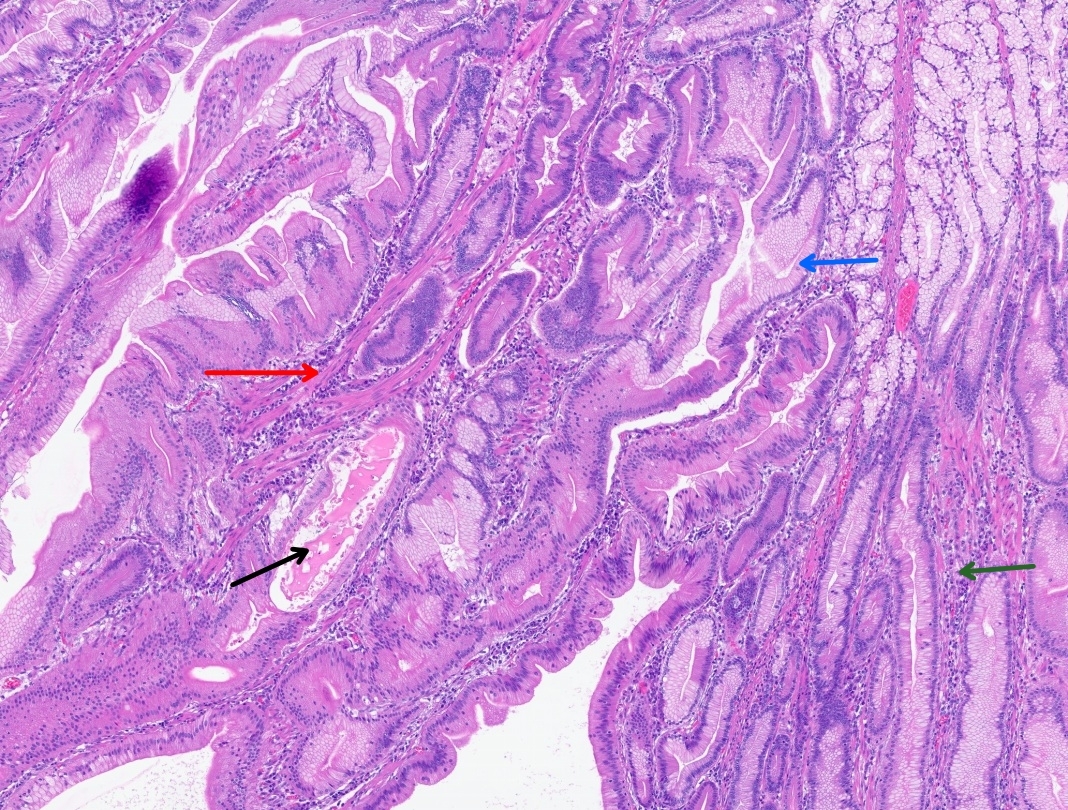

CT abdomen and pelvis with enterography showed numerous intraluminal small polyps in the jejunum largest measuring up to 4.5 x 2.6 cm, 3.0 cm polyp in the left lower abdomen, short segment small bowel intussusception with a polyp as lead point in the right abdomen without associated bowel obstruction or inflammatory bowel thickening, reactive mesenteric lymph nodes and splenomegaly (14.8 cm) (Figure 2). Esophagogastroduodenoscopy and colonoscopy were done, which showed few sessile and semi-pedunculated polyps measuring 4 - 10 mm in the ascending, transverse, descending, and sigmoid colon, multiple large polyps (sessile, semi-pedunculated, and pedunculated) measuring 6 - 20 mm in the rectum, multiple 3 to 8 mm sessile polyps in the gastric fundus and gastric body and a single 15 mm pedunculated polyp at the pylorus. There was no bleeding, and no stigmata of recent bleeding. Polypectomy of a pyloric polyp was done, and histopathology showed features of a hamartomatous polyp with arborizing compact bundles of smooth muscle (Figure 3). Genetic testing was positive for a heterozygous pathogenic variant [c.256C>T (p.R86*)] in the Serine/threonine kinase 11 (STK11/LKB1) gene, establishing the diagnosis of Peutz-Jeghers syndrome (PJS). She mentioned that her parents had screening colonoscopies, which were normal, and denied any family history of PJS. After 5 days of hospitalization, her hemoglobin level remained stable, and there were no overt signs of bleeding. Hence, she was discharged on ferrous fumarate 325mg every other day, ascorbic acid 500 mg twice daily, and folic acid 1 mg daily. Her hemoglobin at discharge was 5.0 g/dL, improved to 10.9 g/dL at 4 weeks, and to 14.0 g/dL at the 4-month follow-up.